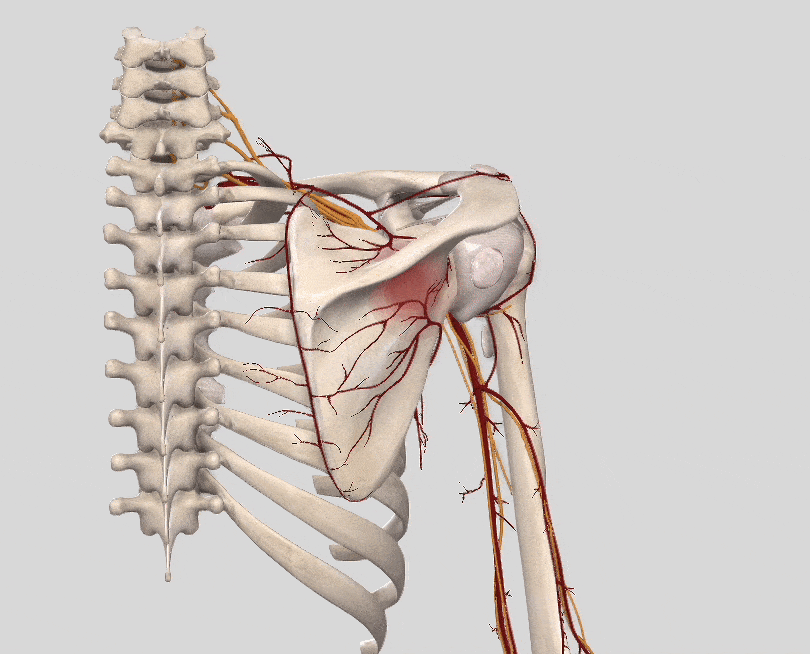

• 肩甲上神経損傷(けんこうじょうしんけいそんしょう)

肩の後ろ外側の痛み、肩全体の疲労感

棘下筋を支配している肩甲上神経が、投球のフォロースルーのような動作のときに引っ張られたり、圧迫されたりして損傷をおこしたものです。野球の投球の他、テニスのサーブやスマッシュ、バレーボールのスパイクなどでも起こります。

肩の痛みが肩の後ろ外側に放散します。肩甲骨の山が目立つようになります。肩全体に疲労感があります。

肩甲上神経のイラスト